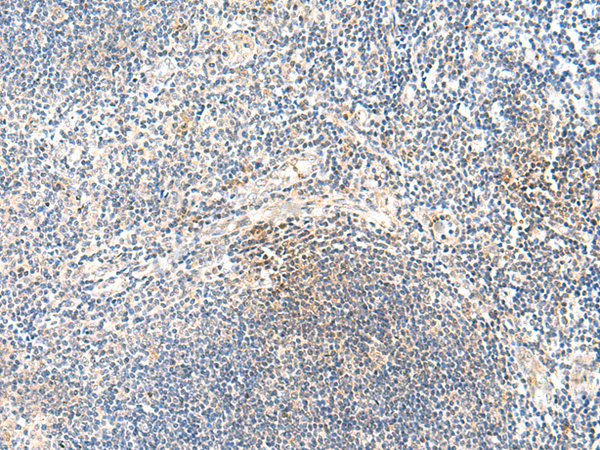

分类: 科研抗体货号: P12436别名: YAP; YKI; COB1; YAP2; YAP65应用: IHC反应种属: Human, Mouse, Rat